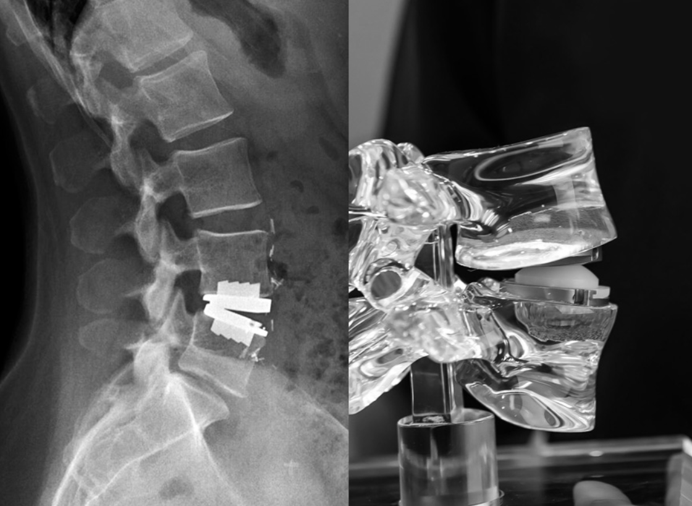

He received his spine training from the renowned Sir Ganga Ram Hospital, New Delhi — catering to over 1500 spinal surgery patients every year — and was awarded the degree of FNB (Fellowship National Board, Spine Surgery). FNB Spine Surgery is the only NMC-accredited fellowship of Spine Surgery in the country.

Dr. Khanna is also the recipient of the prestigious AO Spine International Fellowship from the globally renowned Schön Klinik, Munich, Germany, where he received training in advanced Endoscopic and Minimally Invasive Spine Surgery (MIS Spine Surgery).